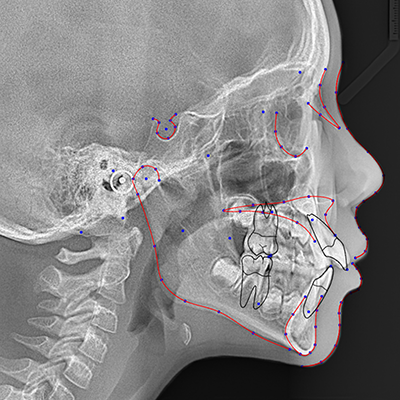

ARTIFICIAL INTELLIGENCE DRIVEN CEPHALOMETRIC ANALYSIS

CephX is an online, all-in-one solution provider for dental artificial intelligence based services, including 2D Cephalometric Analysis. The portal allows you to start a patient record and upload a Ceph x-ray in JPEG/PNG format. Within seconds, you’ll have the full tracing of over 90 landmarks, select any number of analyses to include in a PDF report, and have it downloaded to your device

- Automatic landmark tracing

- Fast, highly accurate, and wide selection of analyses

Our AI performs it all automatically:

- Tracing landmarks

- Scale calibration

- Accuracy estimation

If any of these doesn’t meet our high standards, you’ll see a message that the case is ‘In Review’, and our team of experts will finish the case by the next business day.